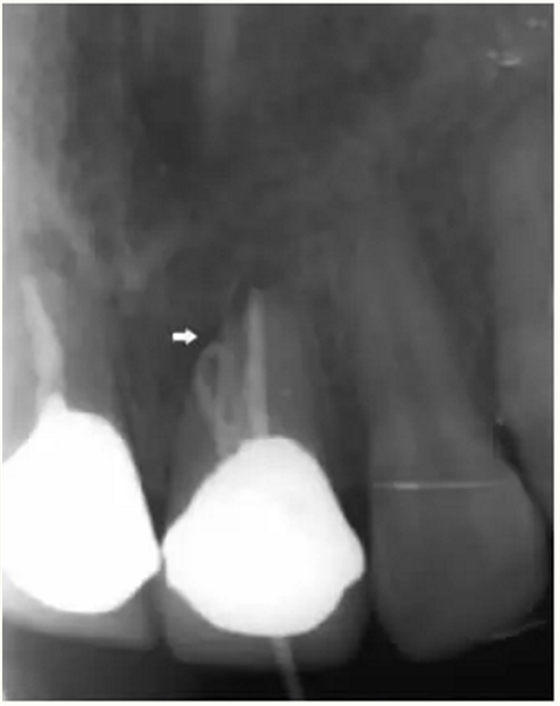

▲牙胶尖示踪显示瘘管与此相通

▲21牙根近中侧位于根尖1/3和根中1/3交界处有牙周膜间隙略增宽

▲术后,X线显示:21根尖切除区域骨质修复,根管倒充填物完好,原牙周膜间隙增宽影消失